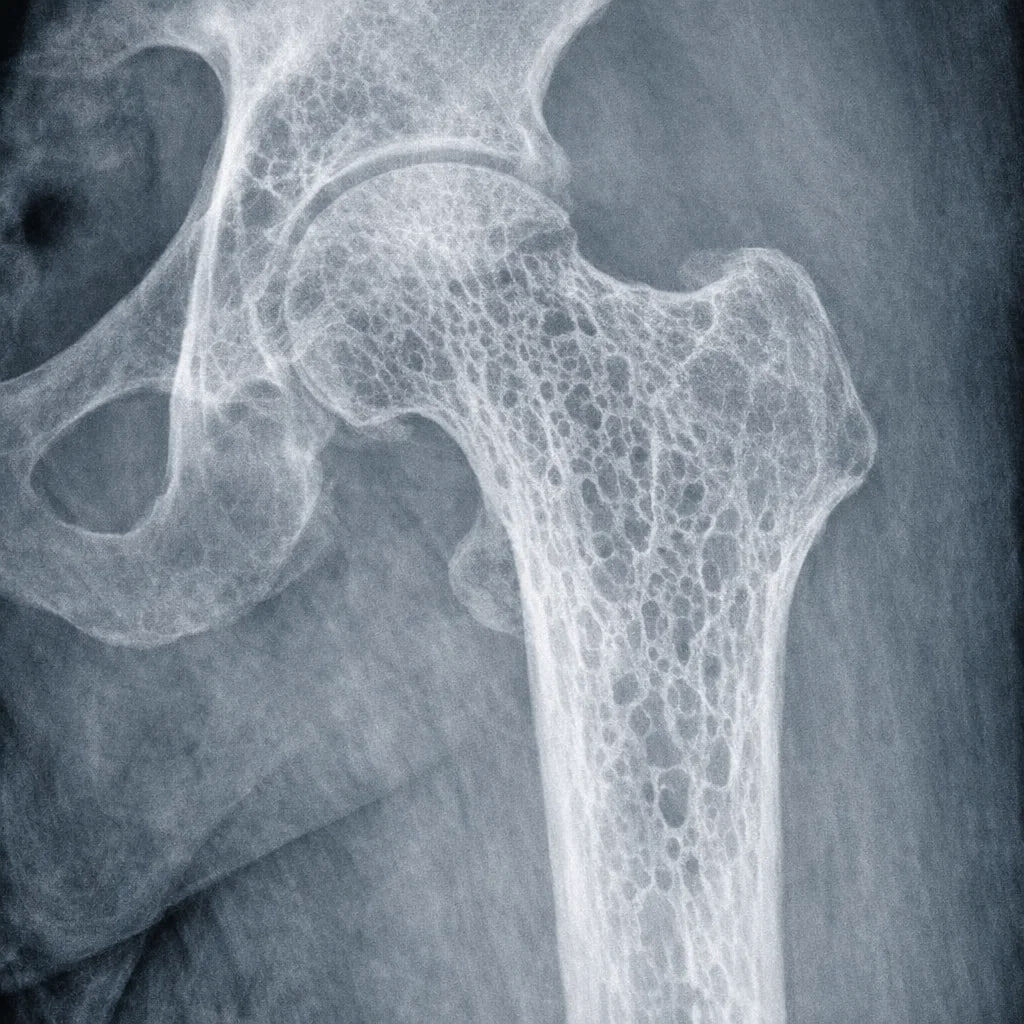

ОСТЕОПОРОЗ 🦴

Снижение плотности костей

До 30–50%, у женщин чаще

Высокий риск переломов